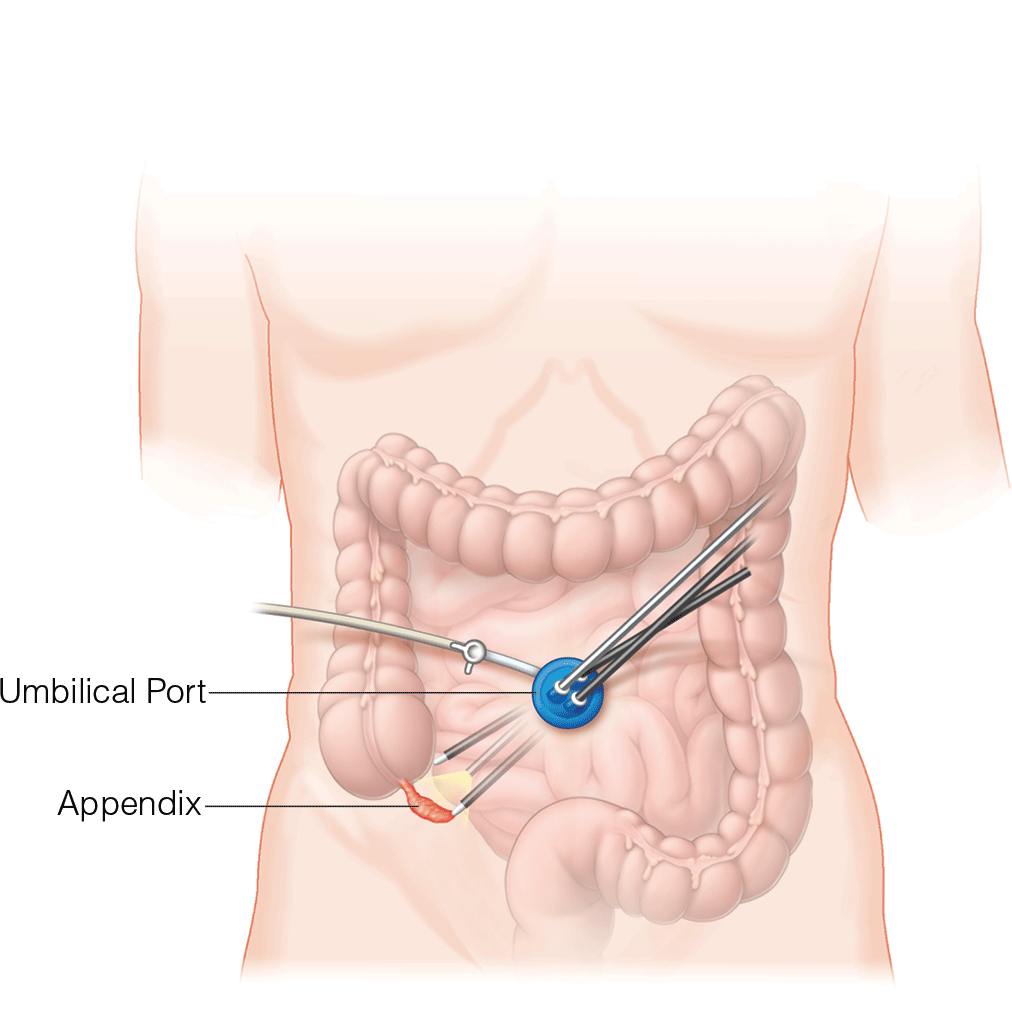

Acute appendicitis remains a therapeutic challenge during active pregnancy. Both laparascopic and open approaches can be considered; the techniques remain largely the same, with a few caveats. Fetal monitoring may be performed using a transvaginal or left lateral abdominal wall approach. For open appendectomy, ultrasonography and magnetic resonance imaging may provide direction for the incision. Laparascopic appendectomies should be approached with a open trocar placement in the midline, with direct visualization. Late-term pregnancies may require alternative approaches in the subcostal region, and the patient may be rolled with their left side down to facilitate exposure of the appendix and relieve pressure on the inferior vena cava.